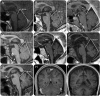

Figure 3.. Brain MRIs of patients with atypical Chediak-Higashi disease (CHD)

Midline MRI sagittal images for 6 patients with atypical CHD obtained at the time of their initial evaluation. (A–F) Patients CHD-6, 19, 24, 17, 23, and 20. The tentorial angle (in degrees) and lines converging on the tentorial angle are represented for each image. (G) Similarly processed image in one representative age-matched control. (H, I) Coronal MRI views at the level of the cerebellar hemispheres for mild (case CHD-23) and advanced (case CHD-20) neurologic impairment demonstrate cerebral and cerebellar atrophy in the more severely affected patient.